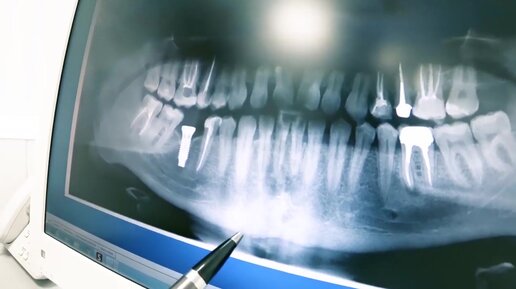

Как расшифровать панорамный снимок зубов?